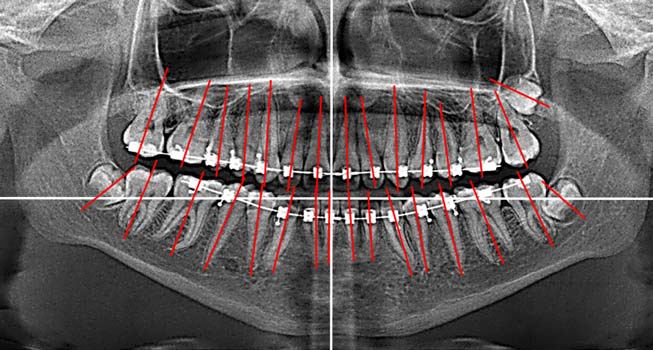

Кроме того, на ортопантомограмме выявили искривление корней постоянных зубов (рис. 7), что затрудняло их перемещение, а нормализация наклона корней при этом не представлялась возможной.

Рис. 7. Ортопантомограмма пациента Л. 15 лет

На ортопантомограмме после завершения ортодонтической коррекции окклюзии выявлены незначительная асимметрия положения зубов и искривление корней отдельных зубов (рис. 9).

Рис. 9. Ортопантомограмма пациента Л. 17 лет

Положение зачатков зубов 2.8, 3.8 и 4.8 в динамике наблюдения от 15 до 17 лет ухудшилось (рис. 10).

Рис. 10. Изменение наклона нижних третьих постоянных моляров пациента Л. относительно окклюзионной плоскости на ортопантомограммах в возрасте 15–17 лет

Это подтверждала динамика наклона осей постоянных зубов и зачатков третьих постоянных моляров относительно окклюзионной плоскости (табл. 3).